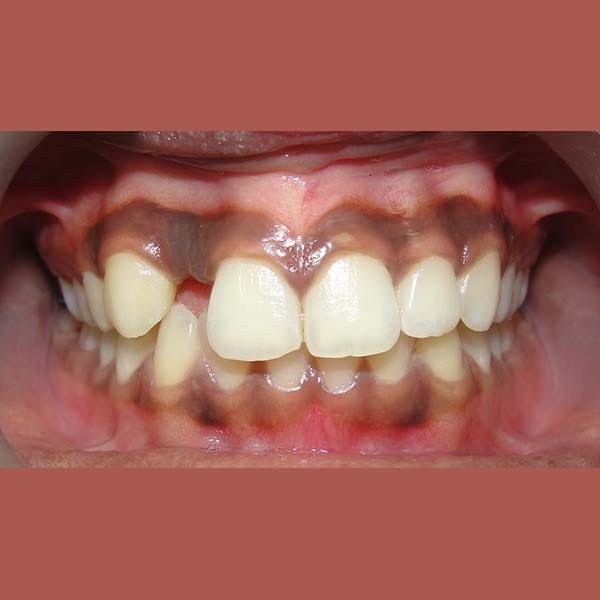

BEFORE